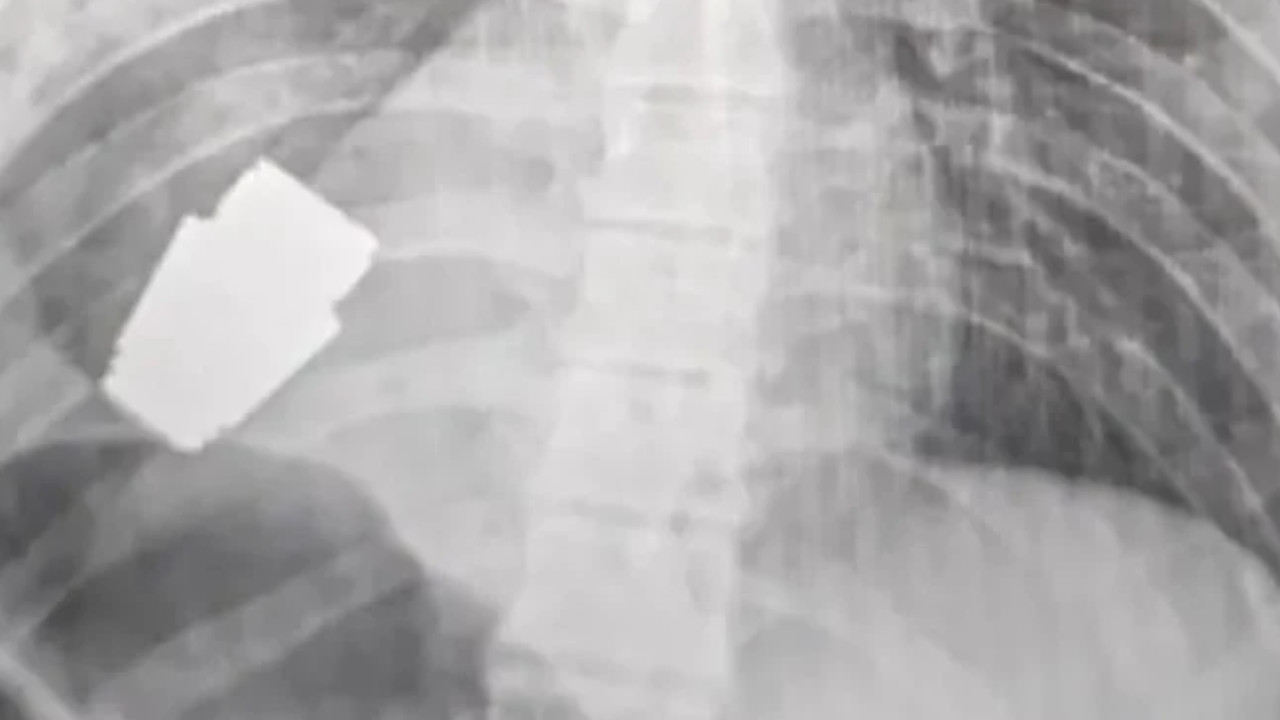

Como un milagro fue catalogada la exitosa intervención quirúrgica que se le practicó a un soldado ucraniano, al extraerle una granada activa incrustada en su tórax, en una región muy cercana al corazón.

La cirugía que se le hizo al soldado de 28 años de edad,se convirtió en un gran reto para el personal medico debido a que la granada podía explotar en cualquier momento.

“Los médicos militares realizaron una operación para extraer una granada VOG, que no se rompió, del cuerpo del soldado”, informó la viceministra de Defensa de Volodimir Zelenski, Hanna Maliar.